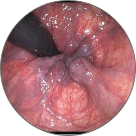

Фекална инконтиненција

Тромбоза на хемороидалните јазли со локална некроза на ткивото

Венозна стаза во патолошки изменети проширени вени

Крвавење од потслизестите крвни садови, што доведува до некроза на ткивото и анемија

Ректален карцином